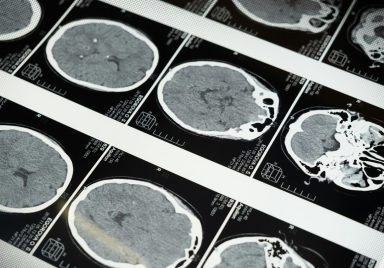

What goes on in the brain of a dying person?